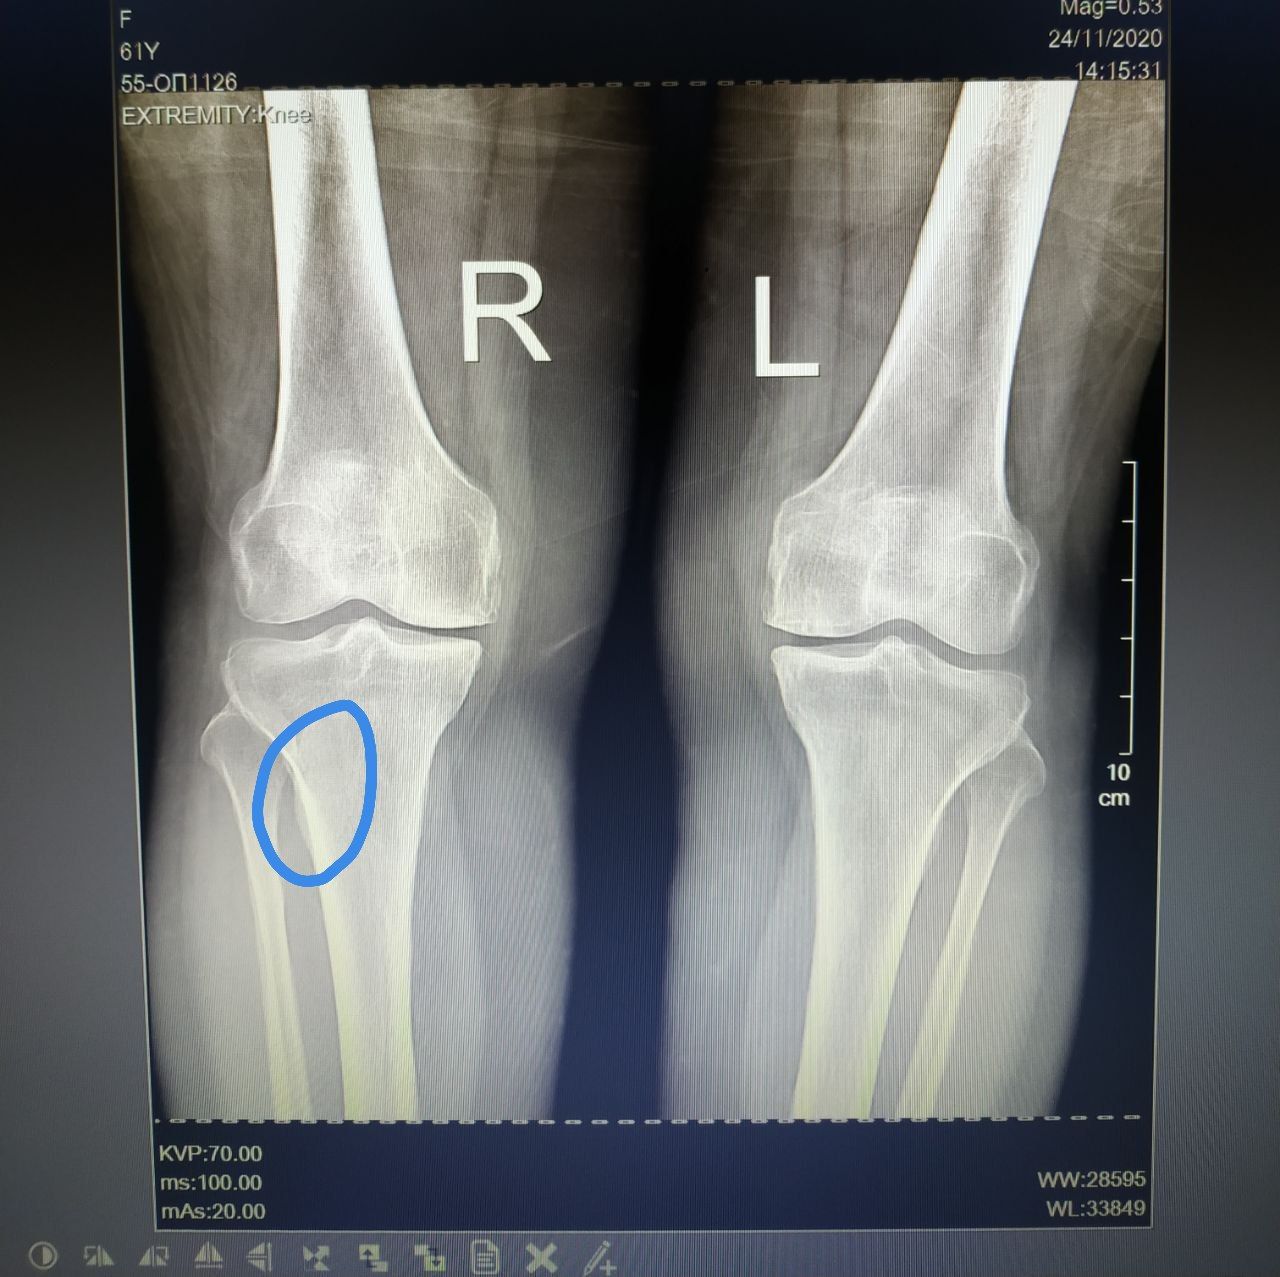

Женщина 61 годиков. Боль в коленных суставах. Ограничение подвижности в коленных суставах

Киста?

Нет

Место прикрепления мышцы

Артроз 0-1 ст